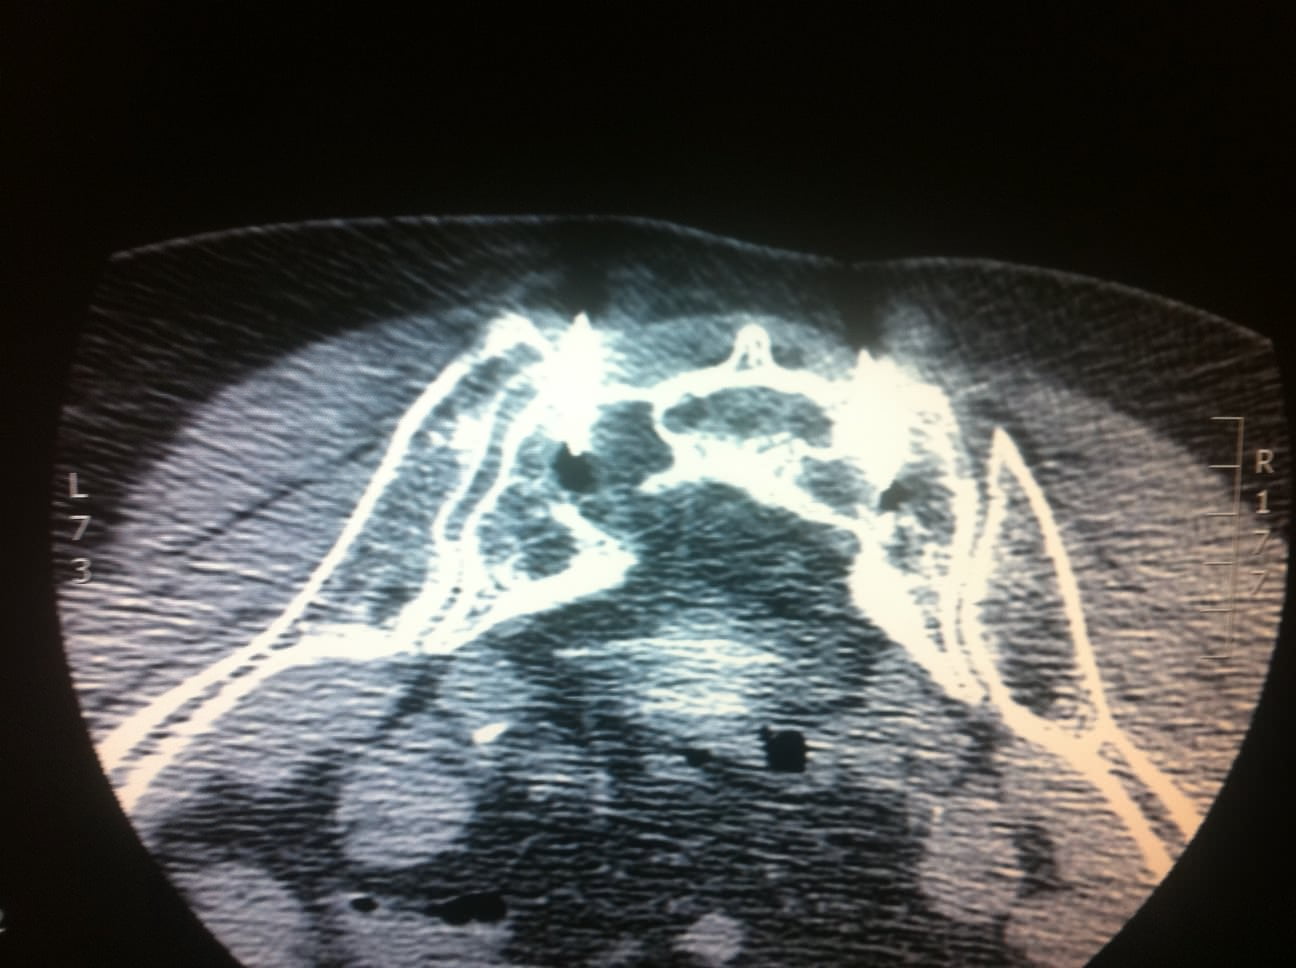

Bilateral sacral fractures (in line with arrows) are clearly visualized

Bilateral sacral fractures (in line with arrows) are clearly visualized Sacrum Fracture Running They have been described in a few case reports, with the injury occurring most. Imaging with ct or mr is pathognomonic. Unlike muscle or tendon pains that might loosen or ease when you move, pain from a sacral fracture usually intensifies during a run, lingers afterward, and progressively worsens over time until. Sacral fractures are often missed or misdiagnosed by. Sacrum Fracture Running.